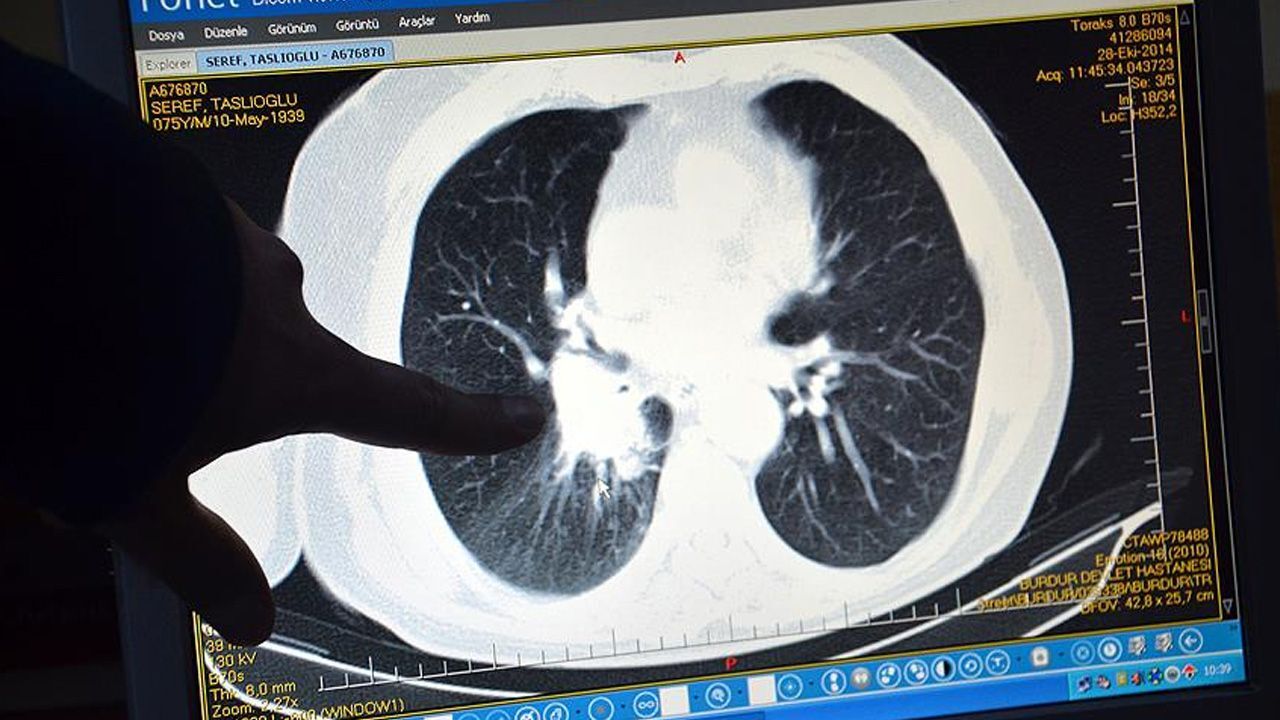

Baş dönmesiyle hastaneye giden babaya yıkıcı teşhis! Doktorlar 6 yıl ömür biçti

İngiltere’nin Cambridgeshire kentinde yaşayan Paul Whitaker, uzun süredir yaşadığı baş dönmesi ve halsizlik şikayetlerinin ardından hastaneye başvurdu. 42 yaşındaki itfaiyeciye hiç beklemediği bir teşhis konulurken doktorlar 6 yıl ömrünün kaldığını söyledi.